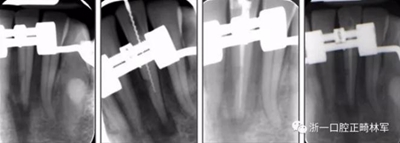

由于下頜中切牙間沒(méi)有間隙行下頜正中切開(kāi)術(shù),故進(jìn)行術(shù)前正畸擴(kuò)展間隙。下頜前牙粘托槽,中切牙托槽成交放置,將中切牙牙根分開(kāi)。使用0.018X0.018鎳鈦絲及置于下頜左、右中切牙之間的推簧推間隙。3個(gè)月后拍攝CBCT示已有足夠間隙行下頜正中截骨術(shù)。

術(shù)后第9天開(kāi)始旋轉(zhuǎn)擴(kuò)弓器,每天轉(zhuǎn)2次,每次轉(zhuǎn)90度,即擴(kuò)開(kāi)0.5mm。每隔1周進(jìn)行檢查,目標(biāo)上頜擴(kuò)開(kāi)9mm,下頜擴(kuò)開(kāi)6mm。18天后,上頜中切牙間出現(xiàn)8mm間隙。下頜出現(xiàn)6mm間隙,(于13天出現(xiàn)后,停止旋轉(zhuǎn)擴(kuò)弓器)。在擴(kuò)弓器旋轉(zhuǎn)3天后,拍片發(fā)現(xiàn)左下頜中切牙遠(yuǎn)中牙根中段有一條低密度陰影,臨床冷熱診反應(yīng)遲鈍,可能為術(shù)中損傷所致。牙體牙髓科會(huì)診,建議行根管治療,故行根管治療。